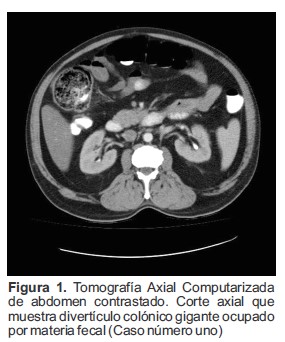

Se realizó Tomografía Axial Computarizada (TAC) de abdomen contrastado en donde se visualizó una dilatación sacular en la región del ángulo hepático del colon ascendente la cual midió 7.0 cm de diámetro antero posterior, 5.5 cm longitud y 6.2 cm transverso. Esta lesión se encontraba ocupada casi en su totalidad por materia fecal (Figura 1) y presentaba un cuello de 31.0 mm de diámetro (Figura 2 y 3), hallazgo compatible con divertículo gigante del colon, además, presentaba ligero engrosamiento de la pared y de la grasa circundante, sin embargo, no se observó gas libre en el abdomen.

Figura 1. Tomografía Axial Computarizada de abdomen contrastado. Corte axial que muestra divertículo colónico gigante ocupado por materia fecal (Caso número uno)

La TAC es el examen diagnóstico de elección no solo debido a su alta sensibilidad, sino que también puede identificar la existencia de comunicación entre el divertículo y el tracto gastrointestinal (4,6). Es un método no invasivo que permite visualizar el tamaño, la localización, el contenido y las paredes, además, es útil para mostrar la presencia de gas extraluminal si se ha producido perforación del divertículo (6,14). Generalmente se observa una cavidad adyacente al colon de pared regular y fina, que puede contener líquido, aire o materia fecal sin realce del contraste (15) (Figura 1).